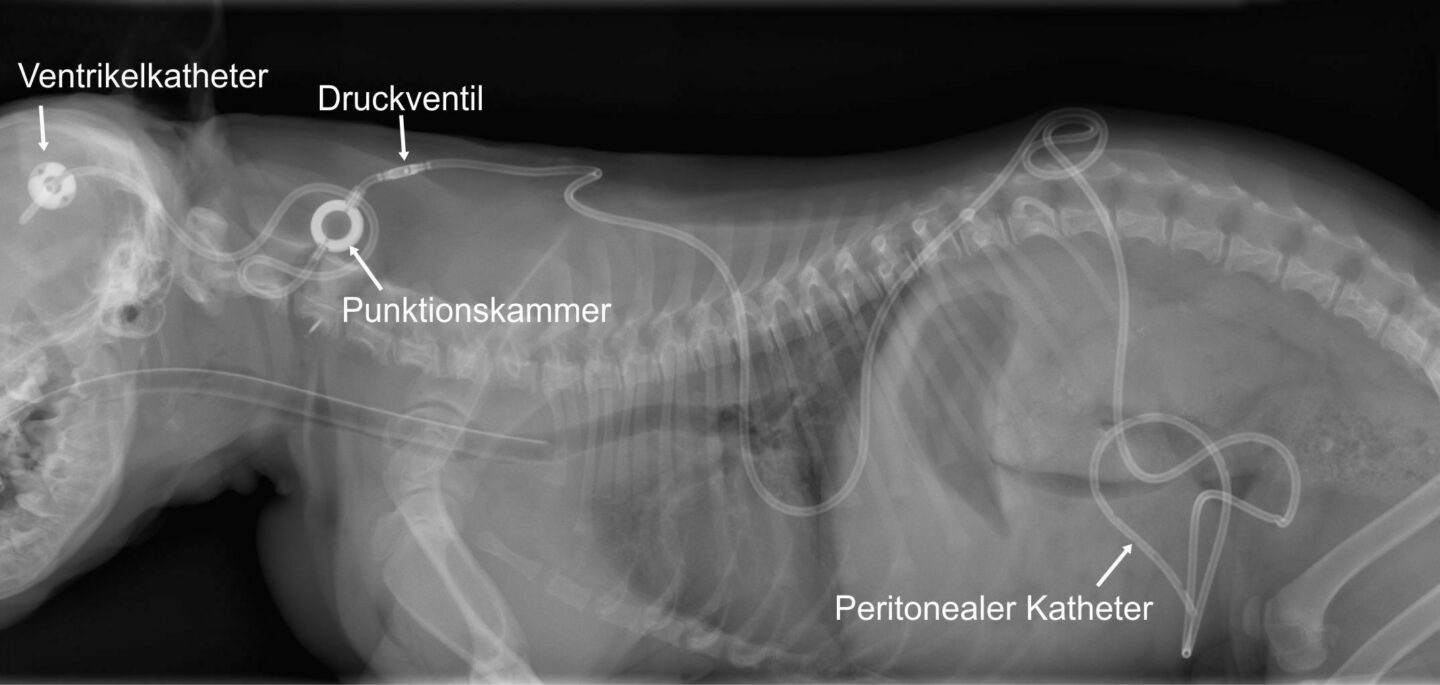

Der Hydrocephalus internus macht beim Hund den Hauptteil der Gehirnmissbildungen aus und stellt eine von wenigen Malformationen dar, die potenziell behandelbar sind. Aufgrund seiner Häufigkeit ist die weitere Erforschung der Grundlagen von Entstehung, Vorbeugung und Therapie des Hydrozephalus ein wichtiges Anliegen des Forschungsteams an der JLU Gießen.